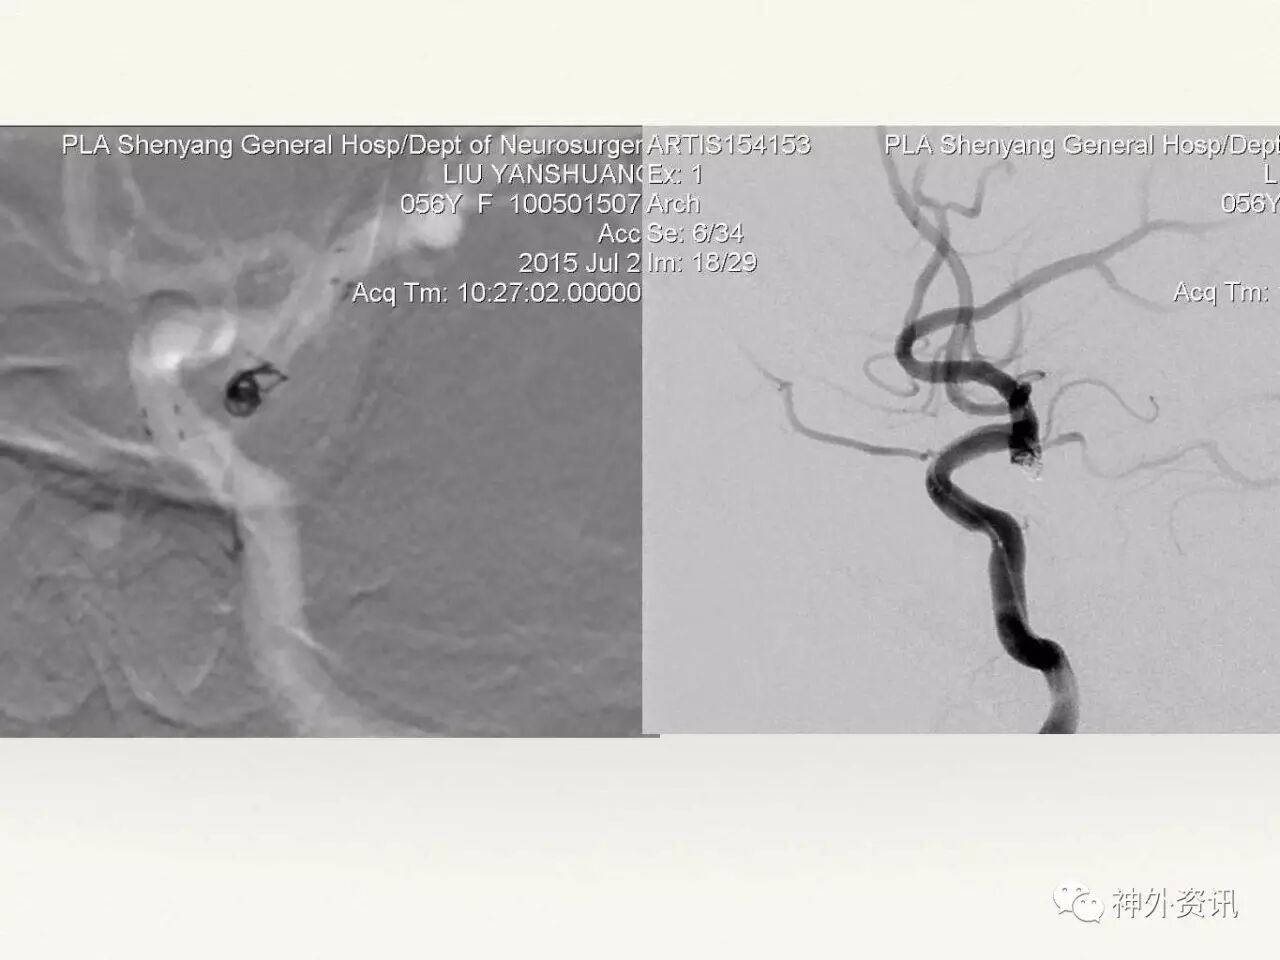

在东北地区率先开展了颈内动脉、大脑中动脉及基底动脉闭塞血管内再通、颅内动脉栓塞急性期取栓、血流导向装置治疗大型宽颈动脉瘤等,对颅内动脉瘤、动静脉畸形、颈动脉及颅内动脉狭窄、颈内动脉海绵窦瘘、硬脑膜动静脉瘘等外科治疗具有较深的造诣。完成脑血管造影8600余例,各类脑血管病介入手术共4500余例,动脉瘤、动静脉畸形、脑肿瘤、脑出血及脑外伤等外科手术1500余例。